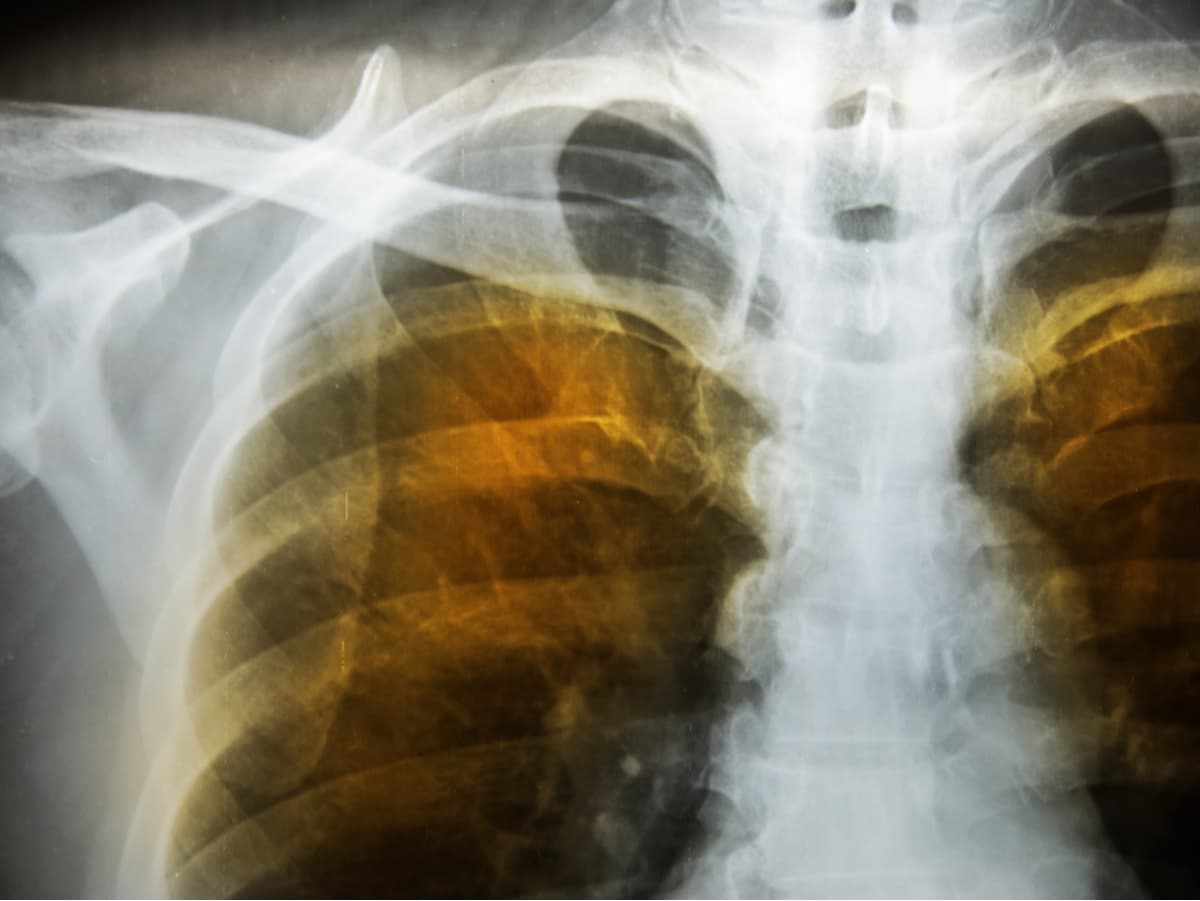

Hastada amfizemde görülen çoğu belirtinin olması hastalık tanısı için yeterli değildir. Fiziksel muayenenin yanında çeşitli testler sonucu hastalığın kesin tanısı konulabilir. Genel olarak akciğer fonksiyon testleri ile tanıya ilişkin kesin sonuca ulaşılır. Akciğerlerin çalışma kapasitesini gösteren ve en doğru sonuç veren yöntemlerden biri, spirometri adı verilen yöntemdir. Spirometri ve benzeri testler aracılığıyla hastalık tanısı konulabilir, hastalığın ilerleyişi takip edilebilir ve uygulanan tedavi yöntemlerinin ne derece etkili olduğu gözlemlenebilir.

Aynı zamanda, göğüs filmi, bilgisayarlı tomografi ve arter kan gazı analizi gibi yöntemler de akciğer fonksiyonlarının ne derece aksadığını ölçmek için kullanılan yöntemler arasındadır.